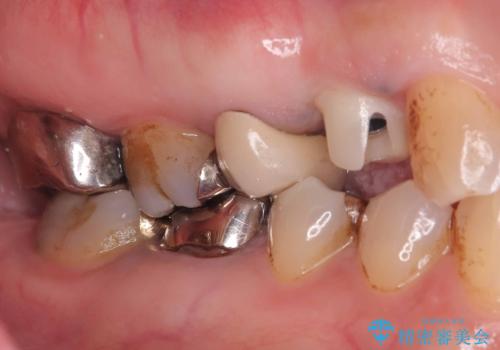

- 「2か月前から歯に違和感があるので診て欲しい」を主訴に来院された患者様です。

被せ物がコア(土台)ごと取れておりかつ根っこも折れてしまっている(歯根破折)状態でした。

歯根破折により保存は不可と診断し抜歯後、骨ができるのを待ってインプラントで治療を行いました。